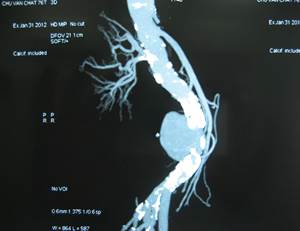

4.5.1.Kết quả:27 BN được mổ có 19 BN mổ cấp cứu và 8 BN mổ có kế hoạch. Có 9 BN khối phồng đã vỡ trong đó vỡ ra sau phúc mạc chiếm đa số, 1 BN vỡ vào ổ bụng và 3 BN vỡ vào cột sống thắt lưng. Kết quả này cao hơn hẳn so với nghiên cứu của các tác giả nước ngoài, AbdelAzim.T.A (20%) [1], Muller (24%)[8], nguyên nhân có thể do thực tế người Việt Nam chỉ đến bệnh viện khi bệnh đã nặng.

Chúng tôi thay mạch Silver Graft loại mạch thẳng cho 14 BN, chữ Y cho 12 BN và bằng miếng vá động mạch cho 1 BN do khối phồng hình túi khu trú (bảng 6). Thao tác khâu vá trên mạch Silver Graft cũng dễ dàng như các mạch nhân tạo khác dù lâm sàng mạch này có vẻ cứng hơn. Các miệng nối đều liền tốt, không cần tăng cường bằng keo sinh học, cũng là một ưu điểm nổi trội của mạch Silver Graft

Hình 3: Phình động mạch chủ bụng vỡ vào cột sống thắt lưng và thay động mạch nhân tạo hình chữ Y

Một BN PĐMCB vỡ vào cột sống thắt lưng sau mổ 48h xuất hiện đau bụng dữ dội và sốc, được mổ lại cấp cứu phát hiện hoại tử toàn bộ hỗng tràng, hồi tràng và đại tràng mặc dù đoạn mạch nhân tạo thông tốt. Chúng tôi nghĩ đến tắc động mạch mạc treo do lóc ĐMCB vì động tác kẹp clamp. Một BN PĐMCB đã vỡ vào khoang sau phúc mạc có tiền sử suy thận độ IV, 10 ngày sau mổ xuất hiện dấu hiệu nhiễm trùng, đau bụng và suy thận nặng lên. Mổ lại phát hiện khối apxe sau phúc mạc quanh mạch nhân tạo, mạch vẫn thông, không bục. Dù đã làm sạch, dẫn lưu apxe, tình trạng nhiễm trùng không cải thiện (có thể do liệu pháp kháng sinh sau mổ ở BN này không có hiệu quả). Cả hai BN mổ lại đều tử vong. So sánh với một số tác giả nước ngoài, trong nghiên cứu của Muller [8]tỷ lệ tử vong tại bệnh viện 36% (12/33BN). Szeberin Z [9] thay mạch nhân tạo tráng bạc cho 42 BN, biến chứng tắc mạch sớm là 8 BN, muộn là 2 BN, 8 BN phải cắt cụt sau mổ, tỷ lệ tử vong sớm 3 BN (8%), muộn 11 BN (38%). Theo Batt tỷ lệ tử vong quanh thời điểm phẫu thuật và trong phẫu thuật là 46% và 21%[7].